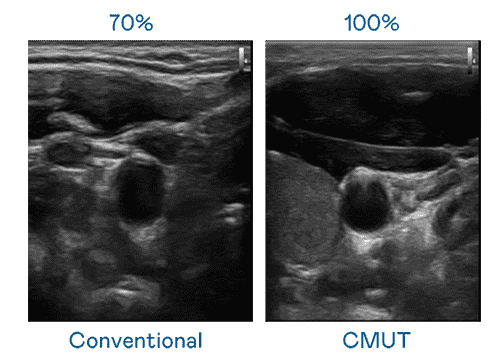

CMUT 技术是一种用电容式微机电元件来产生超音波讯号的技术。。。。与传统 PZT 压电式技术相比,,CMUT 频宽增加 30%,,更宽频的超音波讯号让影像解析度大幅提升,,,是实现高影像品质医疗超音波扫描、、促进精准医疗发展的关键技术。。。

超音波影像的解析度高低,,首先取决于探头能发出的讯号频宽。。。龙门国际 CMUT 可提供高清晰的超音波讯号,,,,提供高频宽、、、、高灵敏度、、、影像纹理细节更高的超音波影像,,,,协助医护人员缩短影像判读时间及利用精准的医疗影像进行诊断。。。。